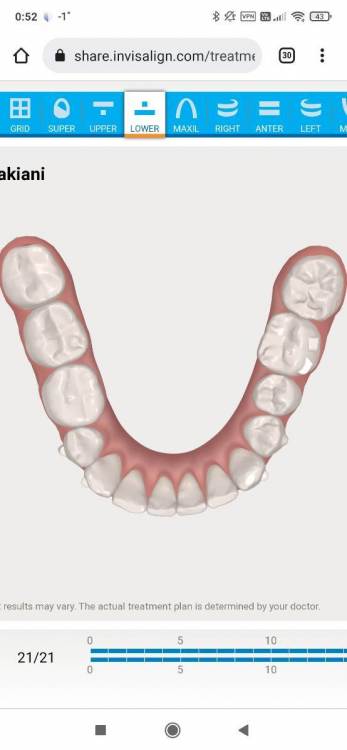

АнтонТЛТ Опубликовано 5 января, 2022 Поделиться Опубликовано 5 января, 2022 (изменено) Нижняя челюсть должна иметь параболическую форму. Видно, что нижний левый первый моляр находится в более язычном положении, его наклон в передне-заднем направлении исправили, но наклон в щечно-язычном направлении остался. Нижний правый второй моляр тоже расположен более язычно по сравнению с соседними зубами. Изменено 5 января, 2022 пользователем АнтонТЛТ Ссылка на комментарий

АнтонТЛТ Опубликовано 5 января, 2022 Поделиться Опубликовано 5 января, 2022 Правый верхний первый моляр так же имеет наклон задних бугров, связано это скорее всего с тем, что нижний правый первый моляр долго находился в разрушенном состоянии и верхний зуб выдвинулся. Нужно поменять наклон верхнего зуба и потом сделать коронку на нижнем. Ссылка на комментарий